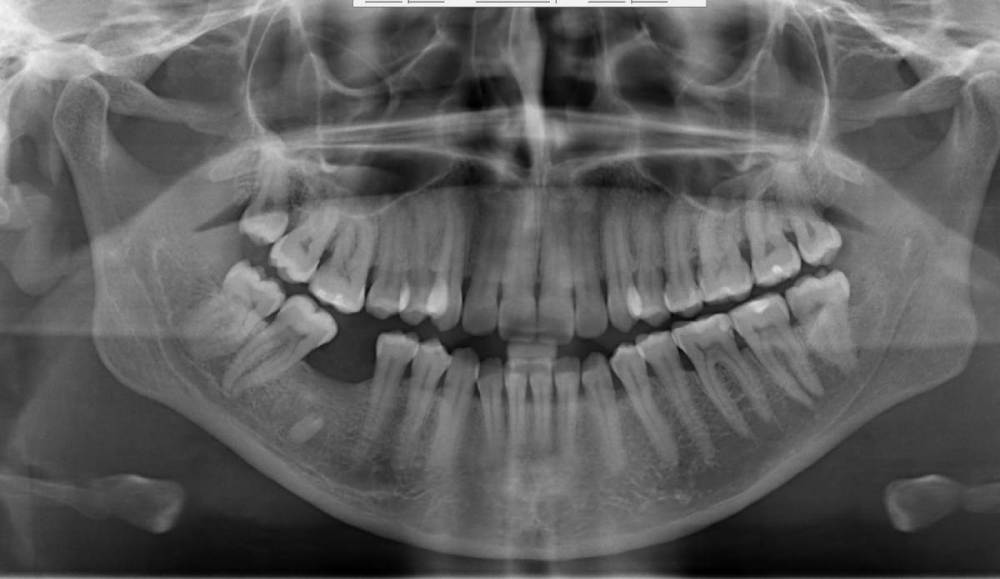

indie Опубликовано 14 июня, 2021 Поделиться Опубликовано 14 июня, 2021 Пациентка 35 лет, жалобы на боли в шеи, горло, ухо, болевые точки за ухом, челюстях, слева, которые появились около месяца назад. Умеренные, не имеют причинного фактора, возникающие в разное время суток. Говорит, что не обращала бы внимания на них, но волнуется нет ли чего-то опасного. Стоматолога порекомендовал врач что бы исключить зубную причину. Холодовые тесты все - зубы витальные. Перкуссия без боли. Только на панораме смутило затемнение канала нижнеальвеолярного нерва слева. Это проблема или артефакт или проекционное какое-то наложение ? Нужно КТ? Ссылка на комментарий

kramer Опубликовано 14 июня, 2021 Поделиться Опубликовано 14 июня, 2021 Исключить на всякий случай синдром Игла (Eagle's syndrome) Ссылка на комментарий

wladdX Опубликовано 14 июня, 2021 Поделиться Опубликовано 14 июня, 2021 Думаю, что никакого затемнения в нижнечелюстном канале нет. Неудачно сделанный снимок: венечных отростков "нет". Ссылка на комментарий